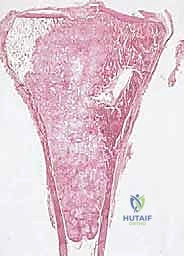

1. ساركوما العظام (Bone Sarcomas)

تنشأ في العظام نفسها وتصيب غالباً الأطفال والشباب. من أشهر أنواعها:

* الساركوما العظمية (Osteosarcoma): الأكثر شيوعاً، تظهر عادة حول الركبة (أسفل الفخذ أو أعلى القصبة).

تتميز هذه الأورام بقدرتها على اختراق الأنسجة المجاورة وتكوين ما يُعرف بـ "المنطقة التفاعلية" (Reactive Zone) أو الكبسولة الكاذبة، والتي تحتوي غالباً على خلايا سرطانية مجهرية. هذا المفهوم البيولوجي هو ما يوجه الدكتور محمد هطيف في تحديد مدى الاستئصال الجراحي.